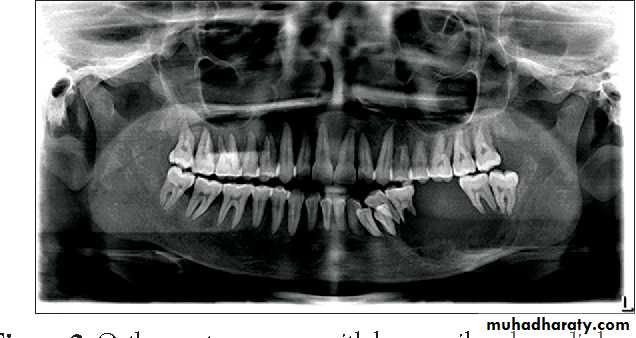

- Radiographically; bilateral multilocular cyst -like radiolucency, teeth seem to be floating within the tumor and may be malformed.- Treatment: surgical contouring is indicated when expansion is sever, leading to functional jaw or airway disturbances, or when the disease causes social problems in the older child. If possible, intervention is delayed until growth has completed.